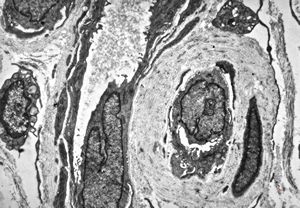

M, 58y. | neurofibroma

M, 58y. | neurofibroma

M, 58y. | neurofibroma